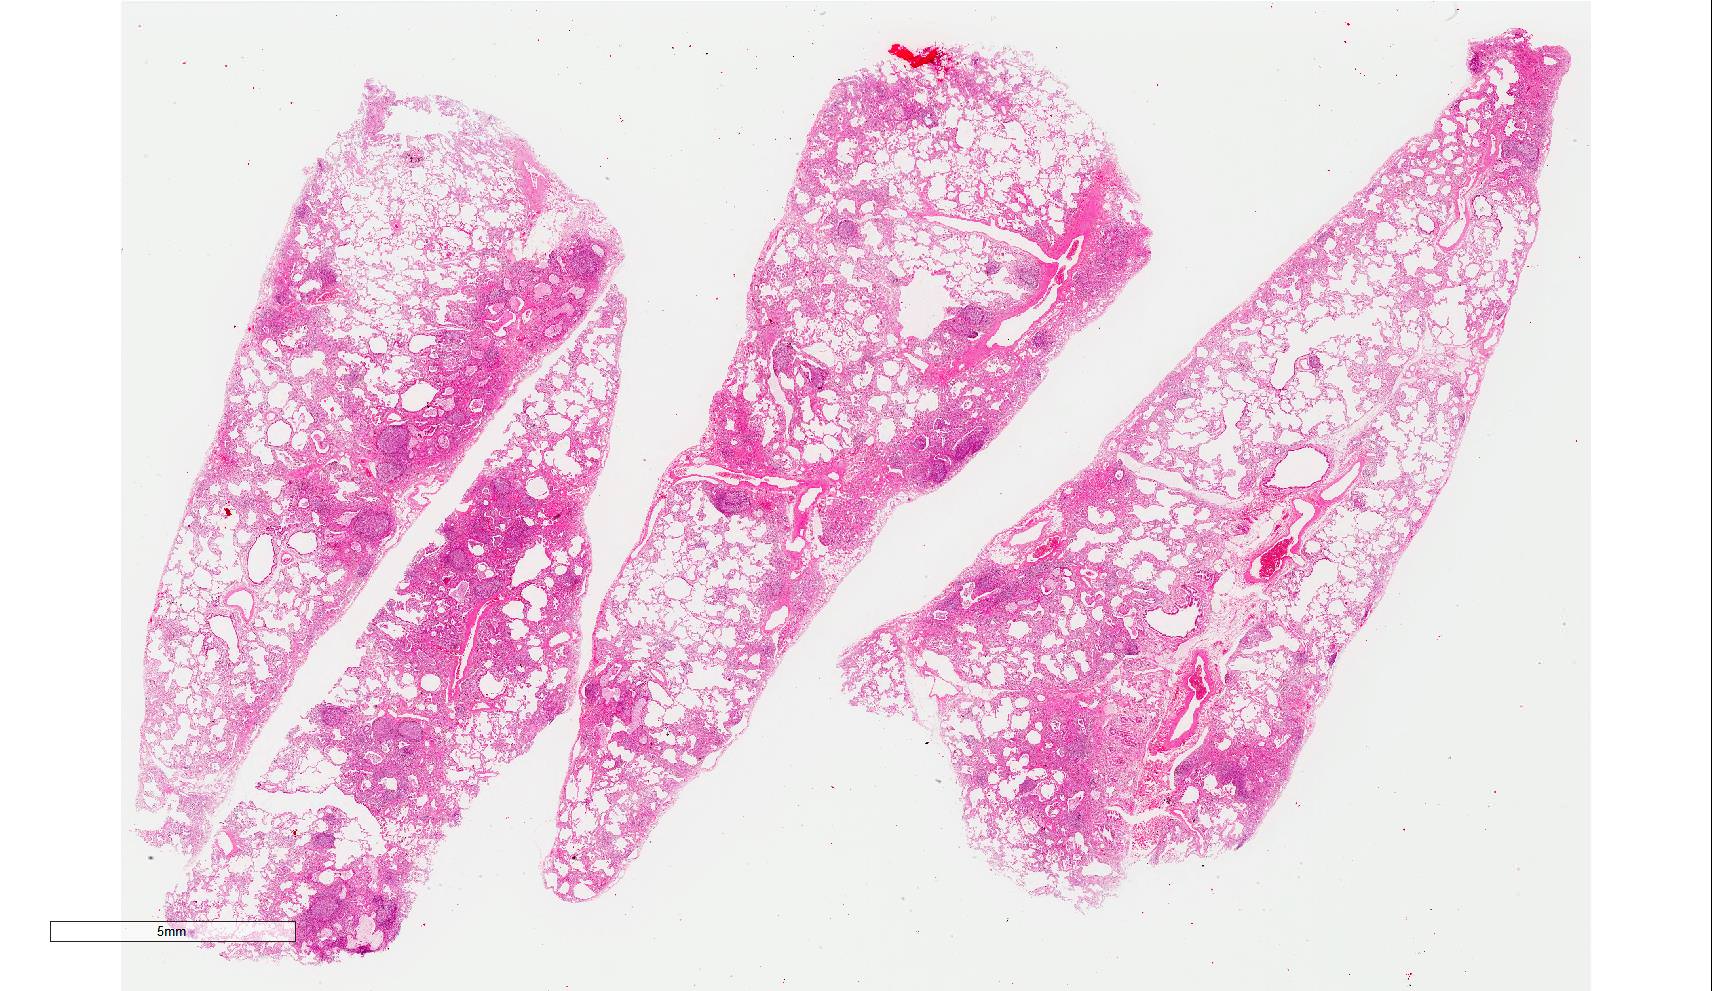

Microscopic (histologic) images

Scroll to see all images.

Contributed by Akira Yoshikawa, M.D.

Gross description

- Diffuse involvement with mild to moderate increase in lung weight

- Fibrotic changes in lower lobes

- Homogeneous and diffuse compared to UIP

- Shrunken lung

- Traction bronchiectasis can be seen

- Honeycomb change can be seen but limited